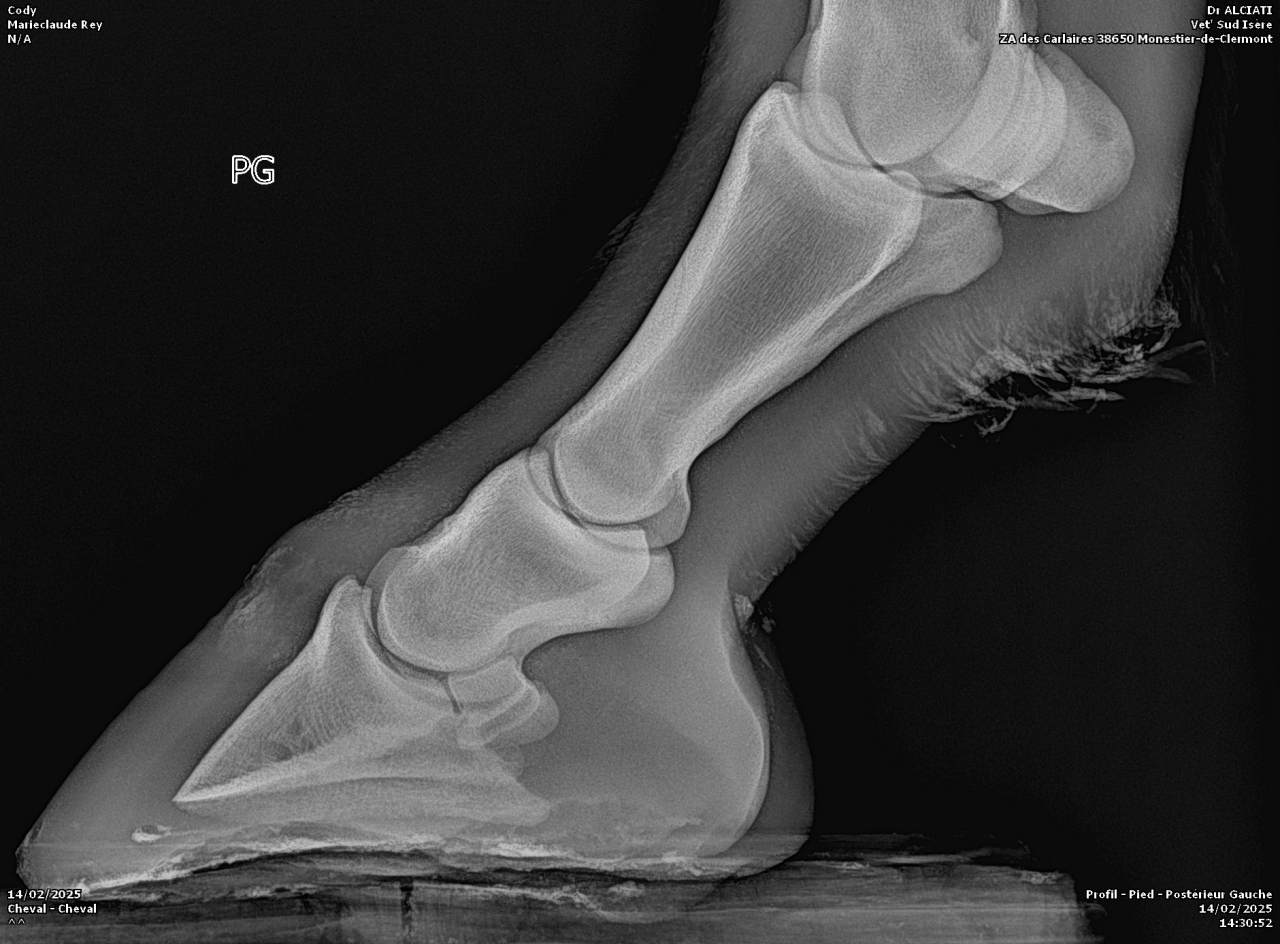

| Dire merci | Voici les radios :![]() ![]() |

DéconnectéDire merci | Personne n'a répondu à tes photos de radios parce que je suppose que comme moi, on ne se sent pas compétent pour l'interpréter. Qu'en dit le véto ? Il a bien dû te donner un diagnostic? Moi je ne vois pas de keratome mais un truc louche sur le processus palmaire du côté droit de la photo. Et l'ensemble qui part quand même bien de travers en vue de face, mais je ne sais pas si c'est dû à la position du pied sur la cale ou si c'est l'angle naturel. Pas l'impression que la sole soit si fine que ça, si? |

| Dire merci | Merci pour la réponse ![]() De ce que j'ai compris, l'anomalie serait la poche de sang (entouré en bleu) : ![]() ![]() C'est de travers car les radios ont été faites sur un terrain en pente. |